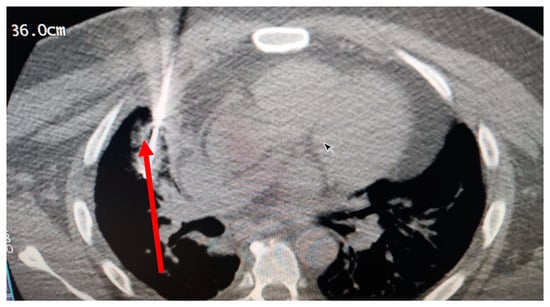

The patient’s history and physical examination as well as recent imaging evaluation should be well evaluated. Chest CT is the key imaging modality for evaluating lung tumor size and the location of lesions. Because of the complaint also of dysphagia, we conducted a CT scan of the chest, abdomen, and pelvis with means of contrast. A biopsy was taken as advised by [52]. The presence of small cell lung cancer, stage IVA (T4 N3 M1a) was confirmed. PET-CT and CT scans show images of a hypermetabolic left pulmonary hilar tumor (Figure 2).

A CT scan and biopsy showed the presence of small cell lung cancer, stage IVA (T4 N3 M1a). The CT scan showed images of a hypermetabolic left pulmonary hilar tumor (Figure 3).

Figure 2. CT scan (left) and Pet-CT (right) images of hypermetabolic left pulmonary hilar tumor from a female SCC patient.

Figure 3. CT scan image showing hypermetabolic left pulmonary hilar tumor from male SCC patient.